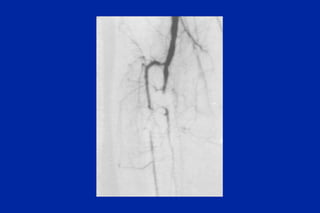

Este documento resume los principales tipos y técnicas de angiografía. Describe brevemente la angiografía, arteriografía, flebografía y linfografía, así como las técnicas de contraste y materiales utilizados. También explica los principales accesos vasculares, la técnica de Seldinger, la angiografía por sustracción digital y algunas técnicas endovasculares comunes.